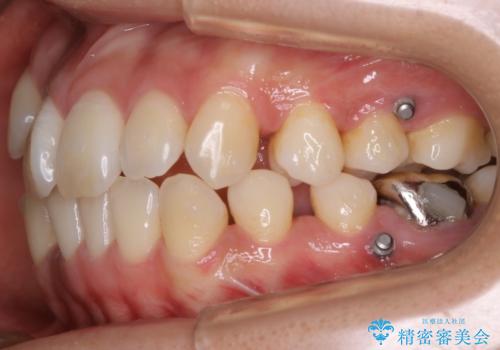

遠心移動

非抜歯で矯正を行う場合にガタつきの改善に必要なスペースを作るために歯の遠心移動を行います。

最初の位置から奥に歯を移動させていくことで前歯のガタつきを改善したり、前歯の位置を後方に移動させることが可能となります。

その反面、歯の移動距離が大きくなるので治療期間が長くなる傾向があり、その分コントロールの難しさが上がることが予想されます。